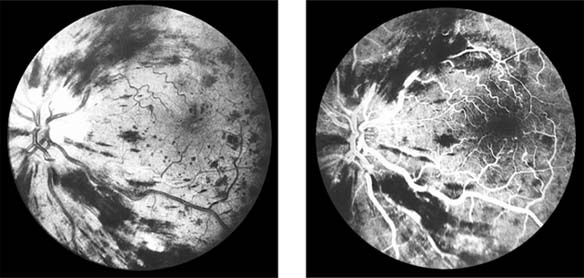

Central Retinal Vein Occlusion (new window  Figure 15-7)

Figure 15-7

Figure 15-7: Central retinal vein occlusion. Left: Photograph shows linear hemorrhages in the nerve fiber layer and punctate hemorrhages in the deeper retinal layers. Right: Fluorescein angiogram shows dilation of the veins.

Fundus examination shows dilated tortuous veins with retinal and macular edema, hemorrhages all over the posterior pole, and cotton-wool spots. The arterioles are usually attenuated, indicating generalized microvascular disease.

The prognosis for vision is poor. Fluorescein angiography demonstrates two types of response: a nonischemic type, with dilation of retinal vessels and edema; and an ischemic type, with large areas of capillary nonperfusion or evidence of retinal or anterior segment neovascularization. In 93% of ischemic and 50% of nonischemic central retinal vein occlusions, the ultimate visual acuity is less than 20/200.

Central retinal vein occlusion has an increased incidence in certain systemic conditions such as diabetes mellitus, hypertension, collagen vascular diseases, and hyperviscosity syndromes (eg, Waldenström's macroglobulinemia, angioimmunoblastic lymphadenopathy). However, the prevalence of cerebrovascular or cardiovascular disease is not increased compared to the general population. Investigations include measurement of serum lipids, plasma proteins, plasma glucose, and assessment of blood viscosity by hemoglobin, hematocrit, and fibrinogen estimations. In young patients, protein C, activated protein C resistance, protein S, and antithrombin III levels should be measured to exclude abnormalities of the thrombolytic system. If hypertension is present, simple renal function tests, including urea and electrolytes, estimation of creatinine clearance, microscopic examination of the urine, and renal ultrasound are indicated.

Treatment of retinal vein occlusion is unsatisfactory. Trials with anticoagulants and fibrinolytic agents have not been successful. In ischemic central retinal vein occlusion, panretinal laser photocoagulation is effective in preventing and treating secondary neovascular glaucoma.

Occasionally, central retinal vein occlusion occurs in young people and may be associated with cells in the vitreous. Rheologic investigations are usually negative, and the prognosis for vision is good.

Retinal Branch Vein Occlusion (new window  Figure 15-8)

Occlusion of a branch vein should be viewed as part of the spectrum of central retinal vein occlusion. Investigations are similar in the two conditions, but arterial disease-particularly hypertension-is common. Branch retinal vein occlusion occurs more frequently in the superotemporal and inferotemporal regions and particularly at sites where arteries cross over veins, and only rarely where veins cross over arteries.

Figure 15-8

Figure 15-8: Retinal branch vein occlusion. The affected segment of retina shows changes of reduced perfusion. This results in irregularity of the arterioles and veins, areas of capillary closure, and dilated capillaries with microaneurysms.

The value of laser treatment in the management of the complications of branch retinal vein occlusion is discussed in Chapters 10 and 24.